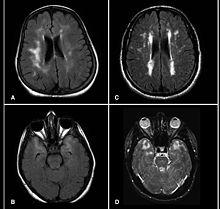

MRI demonstrating white matter changes in the brain of patients with CADASIL

CADASIL is an inherited disorder caused by mutations in the Notch 3 gene located on chromosome 19.[19] The Notch 3 gene codes for a transmembrane protein whose function is not well-known. However, the mutation causes accumulation of this protein within small to medium-sized blood vessels.[19] This disease often presents in early adulthood with migraines, stroke, mood disturbances, and cognitive deterioration. MRI shows white matter changes in the brain and also signs of repeated strokes. The diagnosis can be confirmed by gene testing.[20]